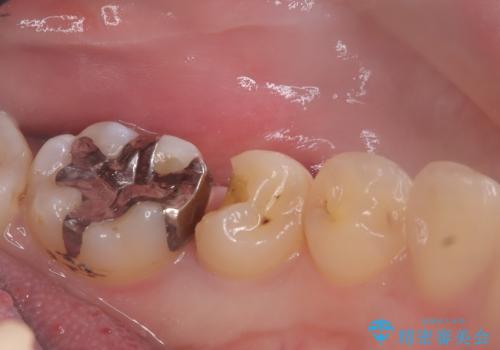

- 主訴:銀の詰め物が取れた、奥の銀の詰め物も一緒に白くしたい

保険適用のメタルインレーの脱離で来院されました。審美性、適合性、清掃性の観点から2本ともセラミックインレーでのやり替えとなりました。

保険適用のメタルインレーはセラミックやゴールドに比べるとプラークなどの汚れが付きやすく、また今回はそこまで大きなう蝕は広がっていませんでしたが、適合性に限界があるためインレーと歯質との境目で二次う蝕が発生する可能性が高くなります。